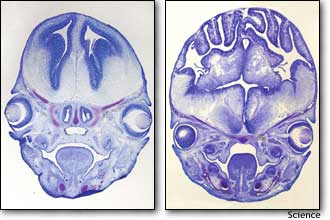

左图是表面平滑、正常的老鼠大脑图,右图则是老鼠被注入经过改造的蛋白质基因之后形成的更大、叠起的大脑图,其看起来很像是人脑图。 据最新一期的《科学》杂志报道,美国哈佛医学院的几位科学家近日利用蛋白质基因工程改造的手段使得老鼠的大脑变大,看起来更像是人脑。科学家表示,虽然这种做法是否会促使老鼠变得更聪明还不得而知,但至少有一点值得一提,那就是一种基因竟然对老鼠的大脑产生如何巨大的影响,这令研究人员始料不及。 研究小组的负责人克里斯托弗-瓦尔什表示:“大脑变大并不一定意味着老鼠会更聪明,因为有时大脑皮层过大可能导致脑部反应延迟。” 上述科学家在研究中利用了一种名为“beta-catenin”、主要用于控制细胞分裂的蛋白质。瓦尔什说:“这种蛋白质可以让细胞停止分裂,从而使细胞变成不再分裂的神经元。”科学家将经过改造的“beta-catenin”蛋白质基因注入到老鼠大脑内部,使得老鼠脑部的神经细胞停止分裂。 结果,老鼠的大脑显著增大,由于头骨容积有限,老鼠的大脑开始像人脑一样叠起,对此,瓦尔什惊讶地表示:“我们没有想到老鼠的大脑会变得这么大,更没有想到会与人脑一样叠起。”事实上,老鼠的大脑通常情况下表面非常平滑,而人脑则布满褶皱并有叠起的现象,因为人脑较大不得不被压挤在头骨里面。 人脑的大小相对于人体而言不成比例,尤其是大脑皮层很大,这里主要由灰质构成,是控制人脑思维的主要区域。瓦尔什表示:“人脑的思维能力主要由大脑皮层的面积决定,如果将叠起的大脑皮层打开,其面积将增加10倍。” (据新浪网) |